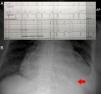

Presentamos el caso de una paciente de 73 años con estenosis aórtica severa, que precisó de estimulación cardiaca provisional en el contexto de bloqueo auriculoventricular completo (BAV) tras el implante de prótesis aórtica autoexpandible Corevalve®. En el estudio ecocardiográfico previo al implante de la endoprótesis se objetivó un gradiente máximo de 82mmHg, y un área valvular aórtica de 0,7cm2, así como la presencia de hipertensión pulmonar severa cuantificada por medición de un reflujo tricuspídeo severo. Su electrocardiograma basal mostró fibrilación auricular asociada a un trastorno de la conducción tipo bloqueo completo de rama izquierda. La estenosis aórtica fue tratada mediante el implante de prótesis percutánea Corevalve® de 26mm por vía femoral, sin complicaciones durante el procedimiento. En el séptimo día de ingreso, la paciente comenzó con episodios de BAV sintomáticos, y periodos de asistolias de hasta 5 s (fig. 1A). Por este motivo, se decidió ingreso en la unidad coronaria para vigilancia intensiva e implante de un marcapasos provisional vía subclavia derecha previo al implante del generador definitivo. Debido a la insuficiencia tricuspídea severa y su elevada presión arterial pulmonar fue complicado atravesar con el electrodo la válvula tricúspide y lograr una correcta posición que consiguiera complejos ventriculares estimulados. Dada la gravedad de la situación por asistolias repetidas, se decidió emplear el ecocardiógrafo de bolsillo (V-Scan, GE Healthcare) por ventana subcostal, para guiar el paso del electrodo primero a la aurícula (fig. 2A), y posteriormente al ventrículo derechos (fig. 2B). Finalmente el electrodo asentó sobre el ápex ventricular derecho (fig. 1B, flecha) precisando un umbral de 5V para conseguir captura ventricular. El generador se programó en régimen de apoyo a 60 latidos por minuto, evitando de esa manera nuevas asistolias sintomáticas. Tras 24h en la unidad coronaria se implantó el marcapasos definitivo VVIR retirando el electrodo de estimulación provisional.